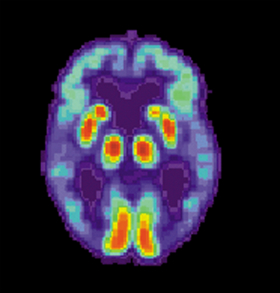

Characterised by memory loss and confusion, Alzheimer’s is the most common form of dementia, usually affecting people over the age of 65.

The cause of the disease is still not known, but research has linked it with brain protein deposits known as beta-amyloid plaques and twisted protein fibres – neurofibrillary tangles – inside the brain.

Picture courtesy of the US National Institute on Aging, Alzheimer’s Disease Education and Referral Center